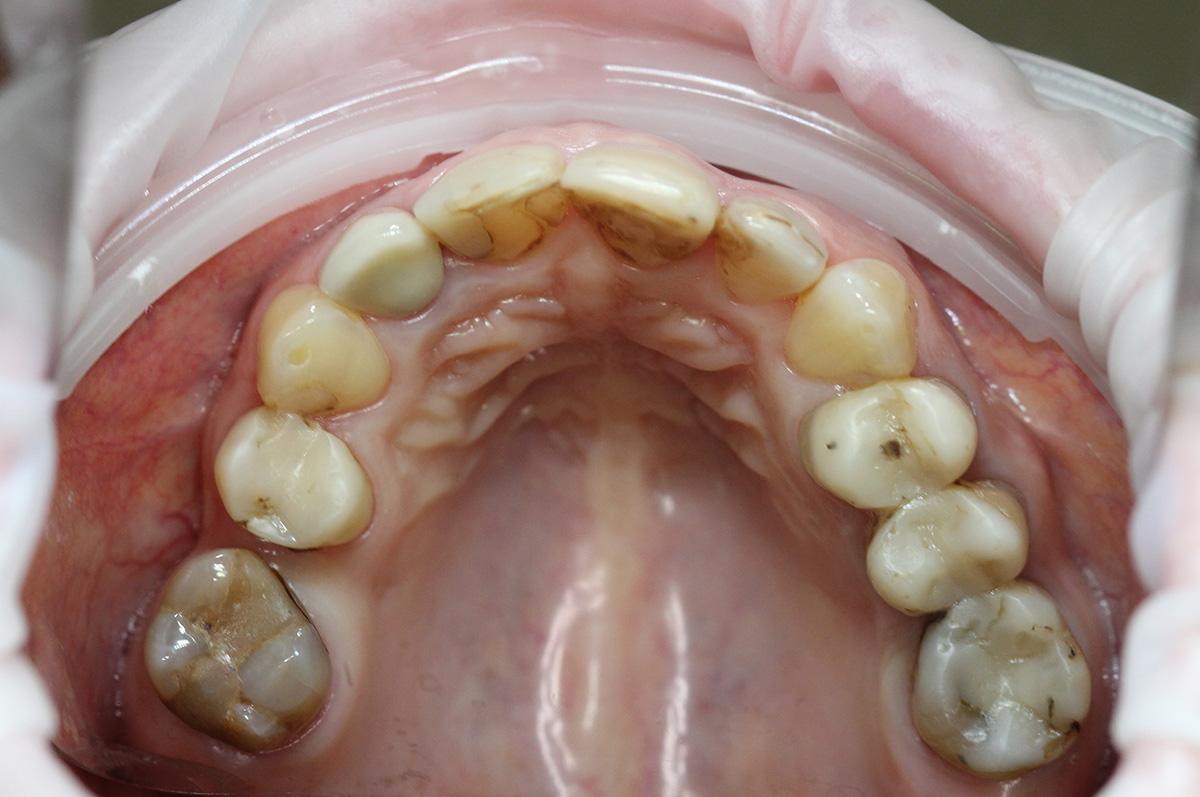

Przedstawiamy metamorfozę naszej Pacjentki, której bardzo zależało na wyprowadzeniu swoich problemów zarówno leczniczo jak i estetycznie.

Pierwszy etap to kompleksowa konsultacja u dr Joanny Zawirskiej-Poły. Podczas tej wizyty zostało wykonane badanie przedmiotowe, podmiotowe, badanie mięśni i stawów, analiza okluzji, badanie stomatologiczne, tomografia komputerowa, rejestracja fotograficzna i długa rozmowa z Pacjentką na temat jej oczekiwań.

Na pierwszej konsultacji Pacjentka dowiedziała się o wszystkich możliwych wariantach działań. Z każdej z przedstawionych opcji zostały również naświetlone wady i zalety danych rozwiązań w perspektywie długofalowej.

Pacjentka, zgłaszając się już na kolejną wizytę świadomie podjęła opcję pośrednią z proponowanych działań: wyleczenie zębów zachowawczo, endodontycznie z zabezpieczeniem protetycznym, estetyczne korekty uśmiechu licówkami, ćwierćkoronami i koronami, jednak bez pełnej przebudowy zwarcia (z zachowaniem starszych odbudów w strefach bocznych, które były wykonane na implantach w przeszłości), która jest zawsze najbardziej polecana, odtwarza prawidłowe kontakty, a także umożliwia lekarzowi i technikowi najlepsze warunki do nadania odpowiednich i harmonijnych kształtów. Te wszystkie działania chronią na przyszłość staw skroniowo-żuchwowy.

Następnie dr Joanna przekierowała Pacjentkę na kompleksowe działania endodontyczne do dr Aleksy Muchy.Po tym dr Joanna mogła przystąpić do działań protetycznych.

Prace protetyczne odbywały się we współpracy z Laboratorium Dental Scan, ściślej z Panią Anną Simierską i Agatą Łatyk-Banasik.